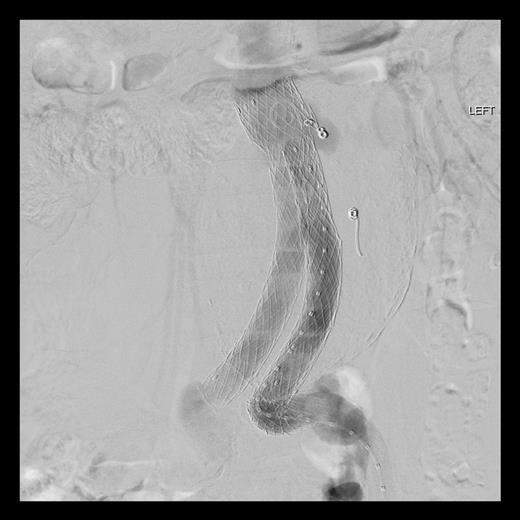

Surgery was performed in hybrid operating theatre. The aorta was accessed via bilateral groin cut-downs to expose both common femoral arteries. Intra-operatively, the type IIIa endoleak was excluded using a right-sided Cook aortouniiliac stent graft (AX1-1-36-116). The left renal arteries were cannulated from the left brachial artery. A PTFE-covered nitinol stent (Atrium V12) was advanced into the left renal artery and deployed in a chimney fashion. The left iliac limb of the stent was occluded using a 20 mm Amplatzer plug proximally and distally with Iliac Plug Zip 24 and 30 mm. Femorofemoral crossover bypass was then performed to complete the surgery. The completion angiography showed adequate sealing with no endoleak (Figs 2 and 3).

The completion angiography showed adequate sealing with no endoleak.